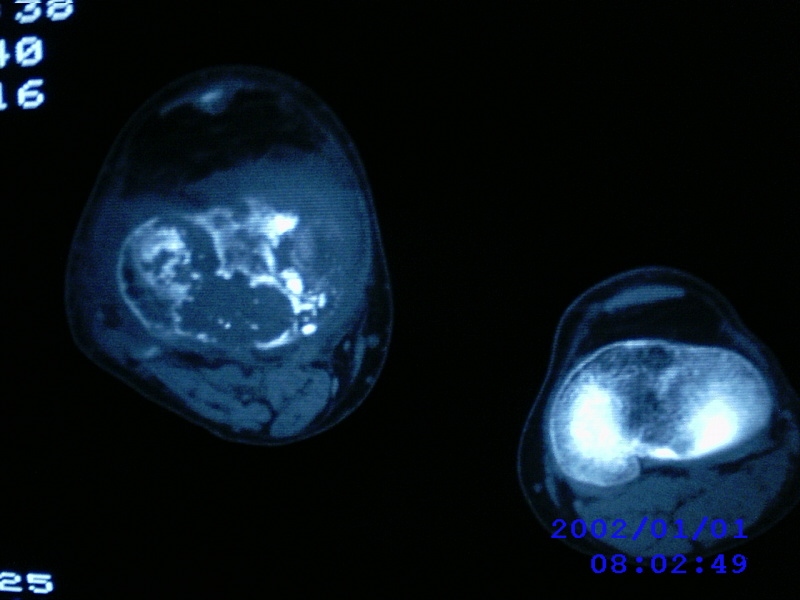

患者,男性,57岁,右侧膝关节疼痛伴肿脹10余年,加重一个月。

关节积液,关节间隙变窄,边缘骨破坏。考虑膝关节tb

关节积液,关节间隙变窄,骨质疏松,多发骨破坏,边缘轻度硬化,近端胫腓骨髓腔软组织充填,患者病史较长,支持考虑结核

有皮质的破坏~有死骨存在

结合临床表现,考虑结核。。。。课医照个胸片

多发骨破坏,骨质疏松,关节积液。考虑右膝关节结核。

资料不太清晰.仅能提示结核可能.